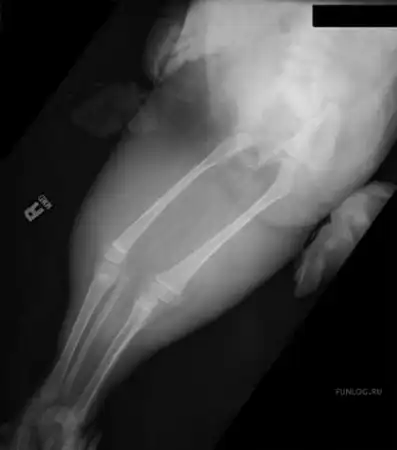

Большинство детей с «сиреномелией» - редким врожденным пороком развития – так называемым «синдромом русалки» погибают в первые часы после появления на свет из-за многочисленных сопутствующих дефектов развития…В настоящее время в мире известны три случая спасения детей с подобным синдромом – это американка Тифани Йоркс, успешно перенесшая операцию по разделению ног 19 лет назад,трехлетняя перуанская девочка Милагрос Серрон, последняя операция по разделению ног которой была проведена летом этого года, и Шилох Пепин, единственная, кого так и не прооперировали…

Кроме сросшихся ног у девочки при рождении не досчитались мочевого пузыря, матки, толстого кишечника, влагалища…У неё была лишь одна недоразвитая почка и один яичник…

Чего не скажешь о Милагрос Серрон… Эта малышка, прооперированная перуанскими врачами в 2006 году, сделала свои первые шаги…

Серьезной проблемой было отсутствие так называемых вертлюжных впадин - суставных ямок для бедер - без них девочка не смогла бы стоять. Однако выяснилось, что постепенно ее скелет сформировал нужные части…